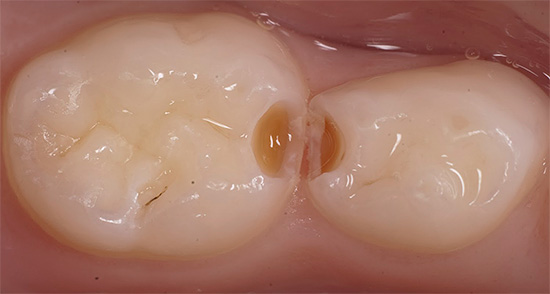

Localização de cavidades em cárie profunda

Hoje, para a conveniência de tratar cáries profundas, os médicos usam a classificação de Black de cáries, dependendo de sua localização nos dentes da mastigação e da frente.

Classe I. Localização do processo carioso em locais de fossa natural e fissuras de pequenos, grandes molares e incisivos.

Classe II Localização de lesões nas superfícies de contato (laterais) de molares e pré-molares (molares grandes e pequenos).